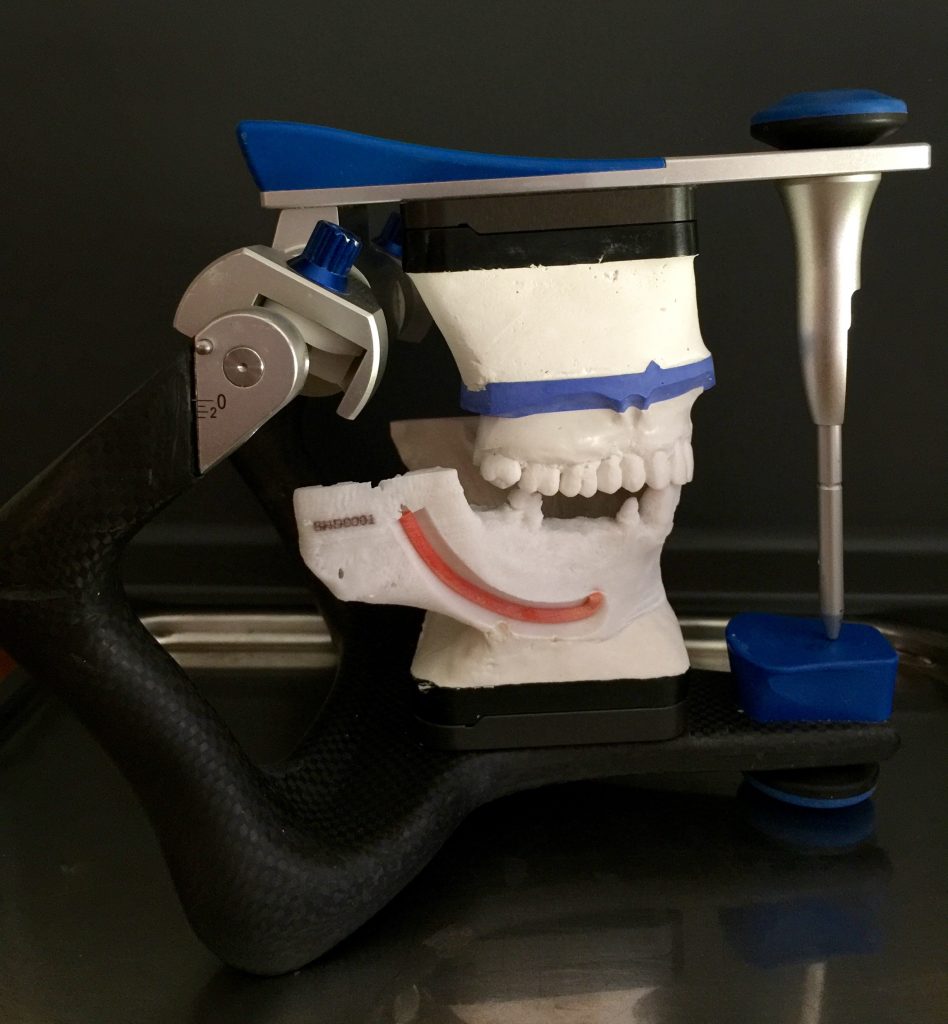

Autores: PRÓLOGO Asimismo, desde el punto de vista pedagógico, el profesional nobel en la materia tiene a su alcance la posibilidad de corregir cualquier posición implantaría en el ordenador, planear los provisionales y plasmarlos en la bio réplica antes de tocar al paciente a operar. Todos estos razonamientos nos llevan a presentar un caso de condiciones muy favorables para poner en práctica estos métodos como primer acercamiento a una Odontología Digital de alta calidad, con medios informáticos, que ya están presentes en la profesión de hoy en día, y será la protagonista única del futuro. Por otro lado, después de numerosos estudios que nos llevan a plantear el “gap” entre implante y pilar(abuttment), como principal responsable de la periimplantitis dado que la microbiota presente en el mismo es imposible de limpiar y en su presencia la cortical ósea reacciona reabsorbiéndose, nos ha llevado a utilizar implantes monobloc ya que los ejes implantarios y protéticos coincidían, y nos permitían su uso. Además, el circonio, ha mostrado a la luz de estudios muy recientes, una preservación y adhesión de los tejidos blandos superiores al titanio, tanto en su tratamiento de superficie de la rosca como a nivel gingival. DESARROLLO Paciente varón de 68 años, con antecedentes de radio/quimioterapia cinco años antes, con Rehabilitación Oral de los cuatro cuadrantes, con una Oclusión Mutuamente Compartida conservada, (REF.8) la que fracasa en el cuadrante 4, 19 años después. El mismo presentaba un puente de porcelana sobre circonio con pilares en 44 y 47, reemplazando el edentulismo de 45 y 46. Se produce la fractura del PM del 44, y ante una endodoncia antigua y corta, se decide implantar las zonas edéntulas, conservando temporariamente los pilares, hasta producida la oseointegración, para entonces también exodonciar el 44. DIAGNÓSTICO Tomamos impresiones del maxilar antagonista, Arco Facial Estático y realizamos montaje del mismo mediante la sistemática ARTEX. Producimos la relajación del músculo Pterigoideo Externo, para obtener la ORC (Oclusión en Relación Céntrica) mediante el método de Laminillas de Long, basado en el concepto de INERVACIÓN RECÍPROCA. Esto nos permitirá montar el maxilar inferior, tanto en su forma de: La primera para practicar la cirugía guiada y comprobar su eficacia, y el modelo de yeso para ser escaneado y confeccionar la GUÍA QUIRÚRGICA. La Biorréplica la obtenemos transformando los archivos DICOM que nos da el CBCT en archivos STL, y a partir de ellos, mediante una tecnología de PROTOTIPADO RÁPIDO, la obtención de un objeto físico en 3D a través de la aglutinación selectiva de una sucesión de capas de polvo. Procedemos a montar la biorrèplica y el modelo de yeso del caso. Podemos verificar la exactitud de las medidas del hueso residual en la bio réplica y compararlas con el scanner. Arrojando un resultado de 8,5 mm de cortical externa a cortical externa. Pudiendo también medir la distancia hasta el dentario. y comparar gracias a la ventana lateral de la biorréplica Dándonos 22mm de distancia. Con lo cual deducimos que implantes de 4,1mm por 12 mm serán perfectamente rodeados de hueso. Medimos también la distancia desde oclusal del antagonista, hasta el hueso desnudo. Lo mismo que, mediante la utilización de la guía radiológica, con un material radiolúcido colocado en gingival de la misma, podemos medir la altura de la encía. Con lo cual podemos calcular la altura del pilar. Es entonces cuando con el programa COC Diagnostix se realiza la programación final: Obteniendo no solo la ubicación, largo, ancho y ángulo de los implantes sino también los provisionales mediante CAD CAM. Ya entonces podemos hacer la práctica quirúrgica en la bio réplica, mediante la guía quirúrgica, instalando los implantes de prueba que no serán los de circonio, ya que la casa no cuenta con ellos, pero si otros de las mismas dimensiones. TRATAMIENTO Entramos ya en la cirugía propiamente dicha. Antisepsia de la zona a operar y zonas anexas. Comprobación del perfecto ajuste e inmovilidad de la G.Q. en boca durante la cirugía. Marcado de la encía y perforación de la cortical. Visión a través de la Guía de la mínima intervención anterior. Comprobación sin Guía. Incisión mínima mesio distal, para apartar y conservar encía queratinizada. Secuencia de drills, perforando a profundidad requerida Observación del Mínimo Trauma Implantes Strauman de Zirconio Monoblock en blíster y montádo en contrángulo reductor. Instalación controlando torque con contrángulo reductor. Comprobación clínica. Comprobación Radiográfica y con Guía. Toma de impresiones, y armado de modelos con técnicas de pasividad protética. Montaje. Resultado de las provisionales ejecutadas por CAD CAM Al no estar conformes con el resultado decidimos desechar dichas provisorias y optar por repetirlas. Nuevas provisorias realizadas mediante encerado convencional. Estado de los tejidos blandos. Provisorias en boca. Oclusión de Estímulo Inmediato. Ref.10: Carga inmediata .Alberto y Diego Bechelli. Comprobación mediante CBCT post operatorio Componentes del equipo (En la próxima presentación, mostraremos las coronas definitivas de porcelana sobre circonio, y la desoclusión provocada por una OCLUSIÓN MUTUAMENTE COMPARTIDA, sobre estos implantes y otros seis mas) REFERENCIAS

FIG: 1-2-3-4

FIG: 5-6-7-8

FIG: 9-10-11-12

A-BIORRÉPLICA

B-MODELO DE YESO

en una posición fisiológica (Oclusión en Relación Céntrica).

FIG: 14-15-16-17-18-19-20